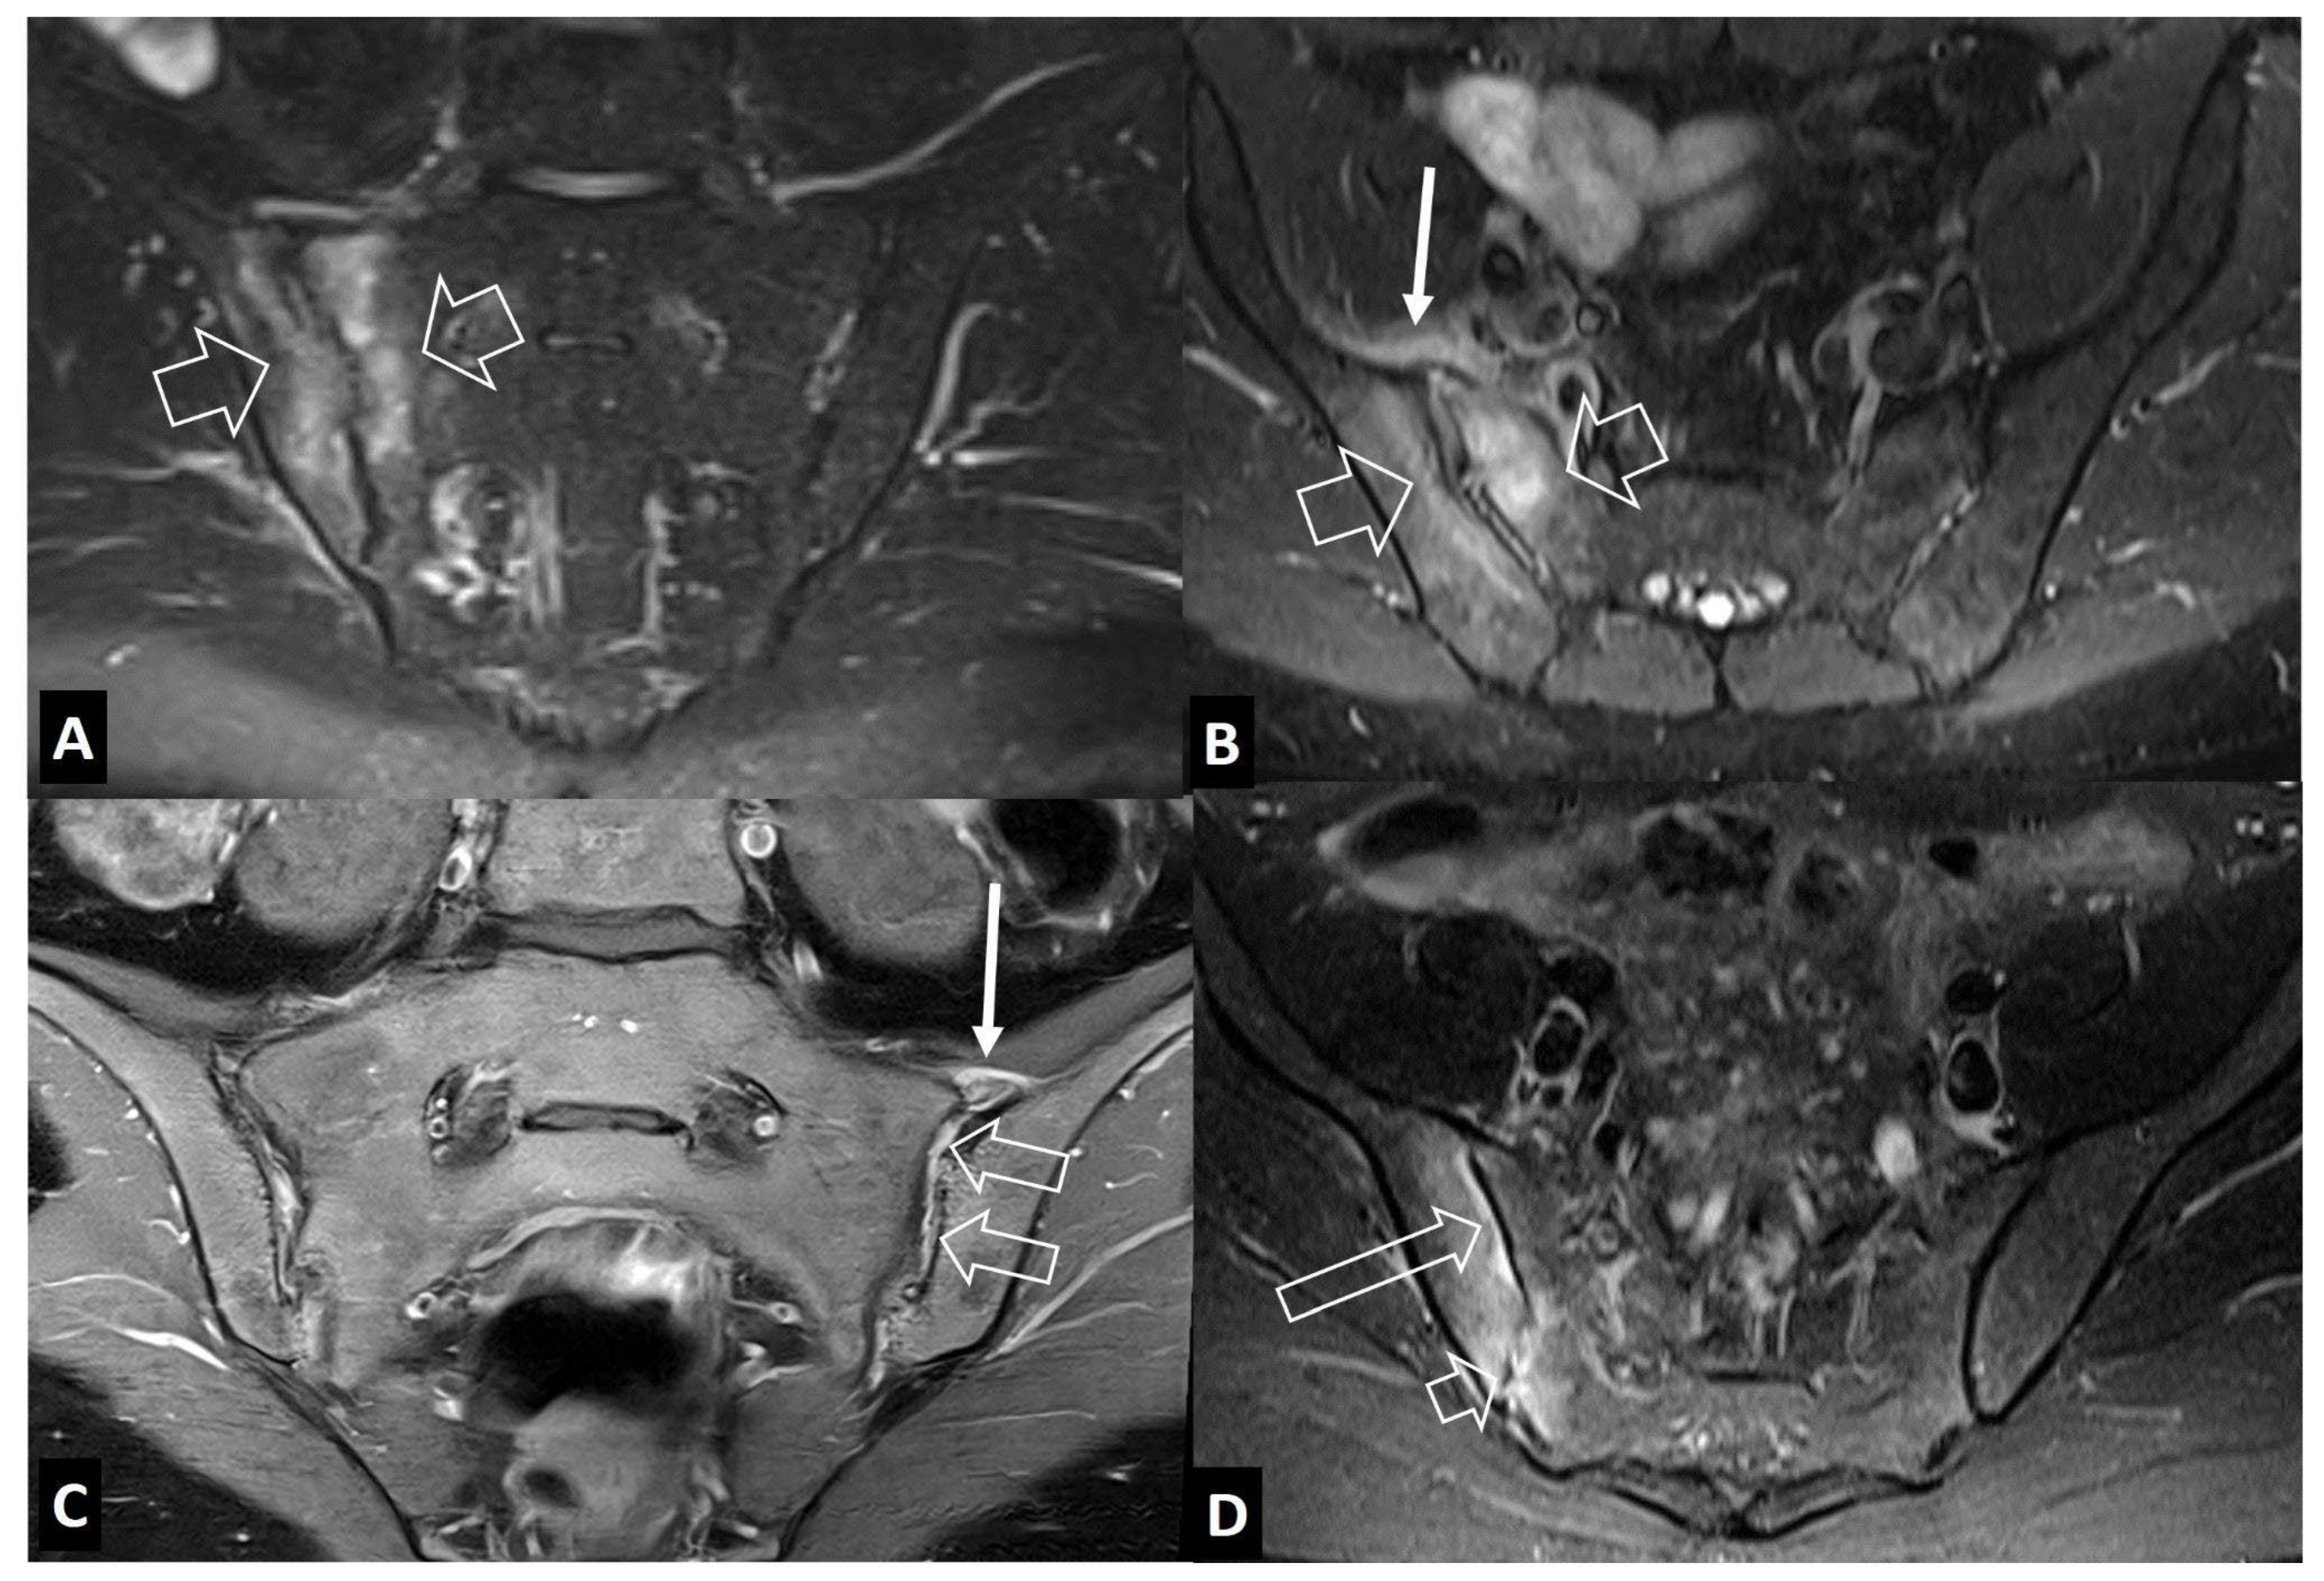

1. b. Non Infectious Sacroiliitis

- Interligator S, Le Bozec A, Cluzel G, et al. Infectious sacroiliitis: MRI- and CT-based assessment of disease extent, complications, and anatomic correlation. Skeletal Radiol. 2023. [CrossRef]

- Kang Y, Hong SH, Kim JY, Yoo HJ, Choi J-Y, Yi M, Kang HS Unilateral sacroiliitis: Differential diagnosis between infectious sacroiliitis and spondyloarthritis based on MRI findings. AJR Am J Roentgenol 2015, 205, 1048–1055. [CrossRef]